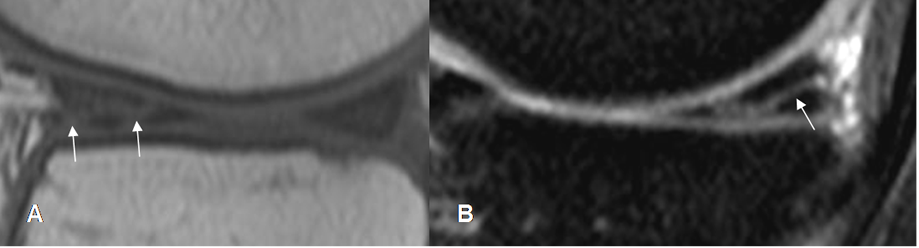

Fig 71. Ruptura meniscal horizontal.

A: RM sagital en T1 y B: RM sagital en STIR. Imagen en sentido horizontal que se comunica el borde libre y la superficie articular inferior, por ruptura meniscal.

Fig 72. Ruptura meniscal vertical.

A y B: RM sagital en STIR. Imagen en sentido vertical que se comunica con la superficie articular inferior, por ruptura meniscal.